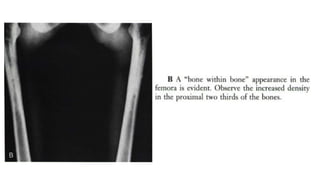

 Other skeletal areas that may be affected by sarcoidosis include nasal

bones, pelvic girdle structures, ribs, and the skull.

 Lesions in the pelvic bones or in the spine may at first lead one to suspect

cancer metastases.

 Highly probable sarcoid arthritis includes the typical features of the

trabecular pattern, osteolysis, cyst formation, and punched-out lesions